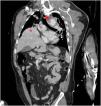

This is the case of a 49-year-old man with closed thoracoabdominal trauma after sustaining a head-on collision in a car crash. The full body CAT scan performed confirmed the presence of a ruptured right hemidiaphragm with herniation of right hepatic lobe (*) towards the thoracic cavity, mediastinal displacement, and traumatic dissection of descending aorta at the ostium of the left subclavian artery ostium (arrowhead) in the oblique coronal (Fig. 1) and cross-sectional views (Fig. 2). An emergency surgical reduction was performed on the diaphragmatic hernia followed by delayed aortography (Fig. 3) with aortic repair through stent-graft implantation. The association between a right hemidiaphragmatic rupture and a traumatic aortic dissection is very rare. A high-energy/deceleration mechanism correlation has been described. These is potentially lethal, but deaths can be avoided with early diagnoses and treatment.